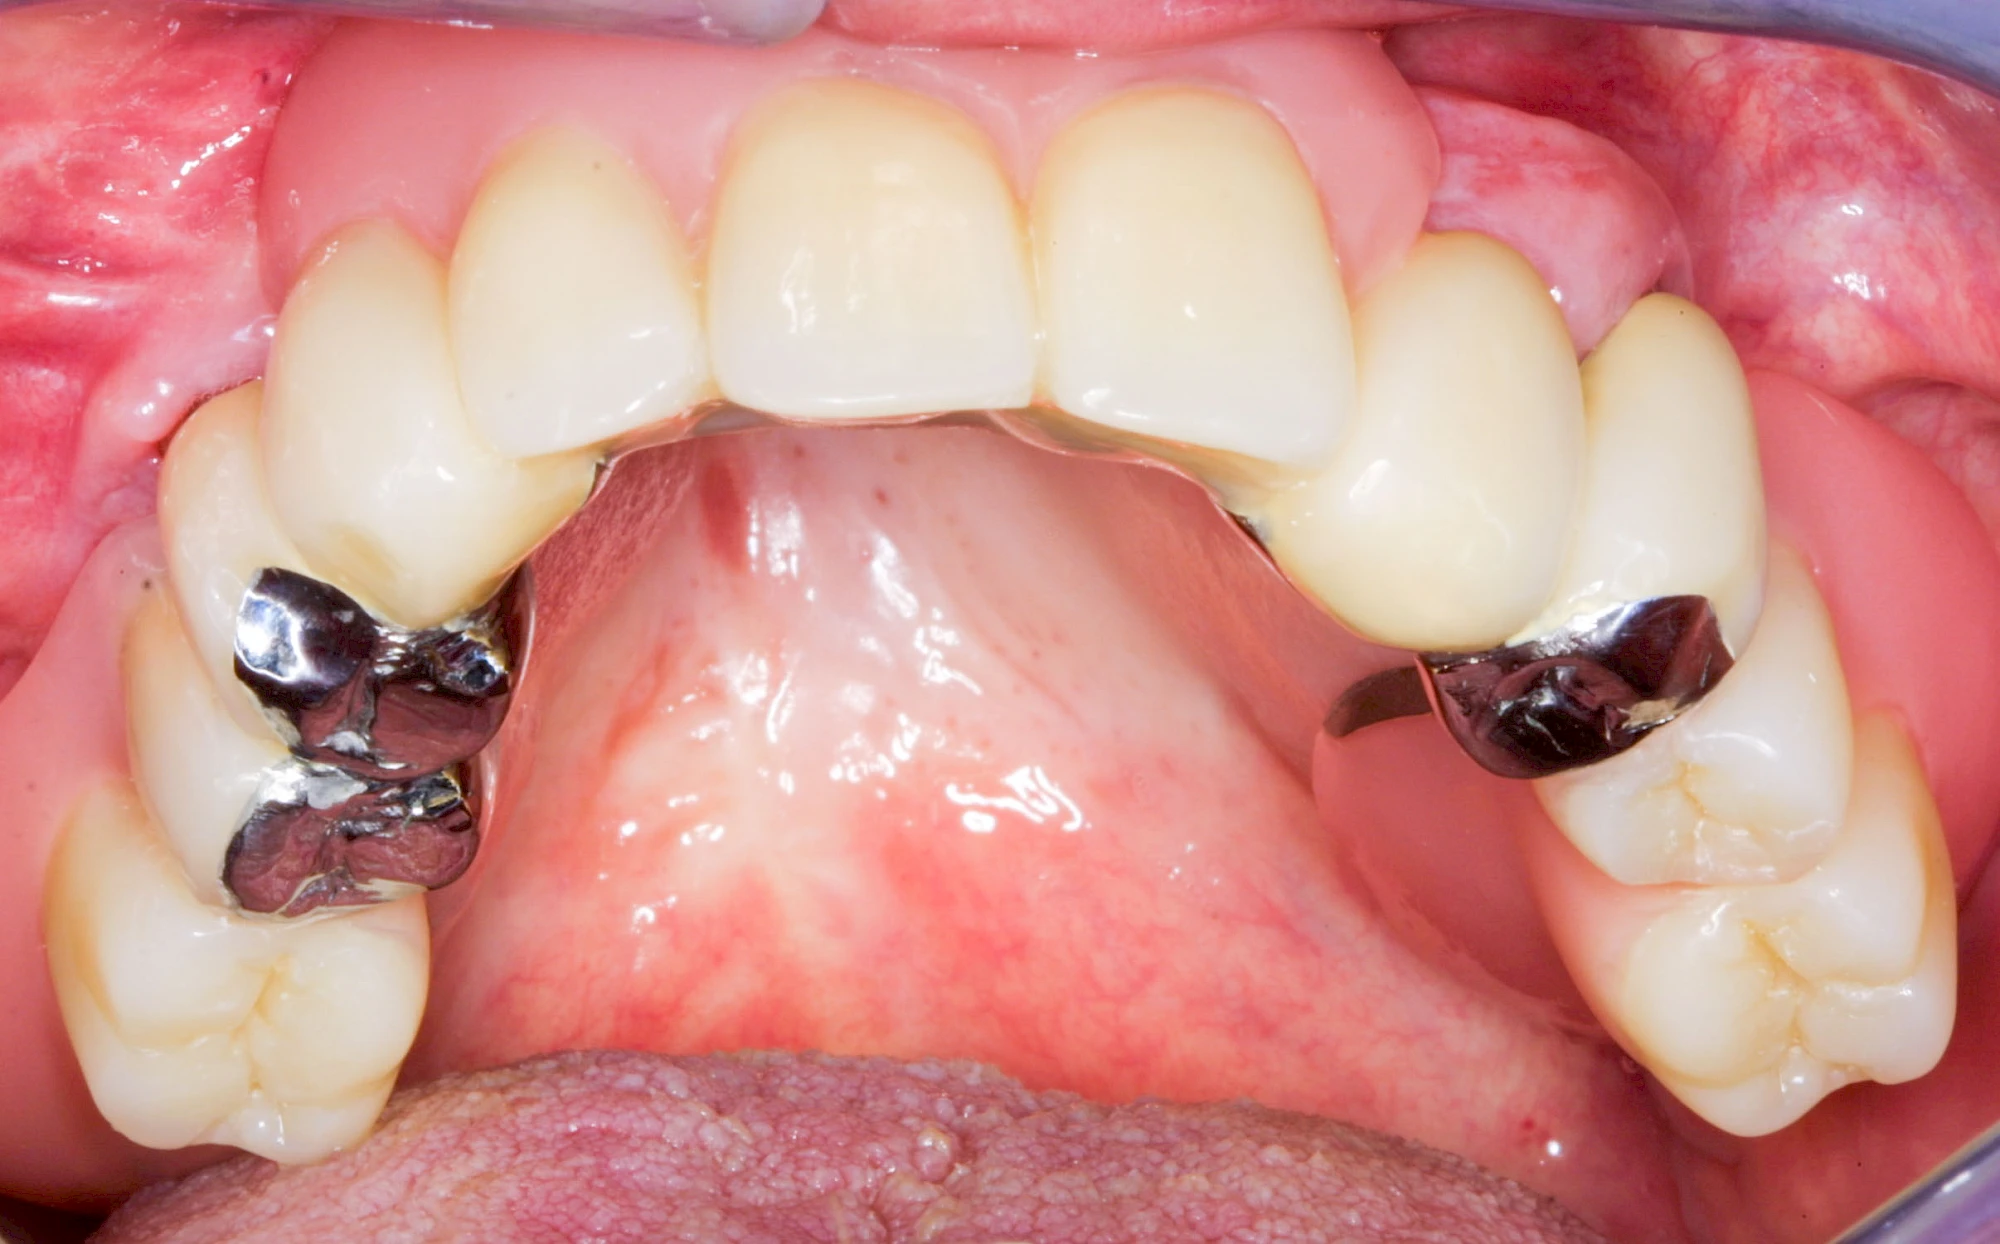

Überbeine im Bereich der Kiefer sind gar nicht so selten. Häufiger im Bereich der Seitenzähne unterhalb des Zahnfleisches, aber auch in der Mitte vom Gaumen. Überbeine haben in dem Sinne keinen Krankheitswert, müssen also nicht operativ entfernt werden, wenn diese nicht stören. Überbeine können ein Anzeichen für Knirschen und Pressen sein.